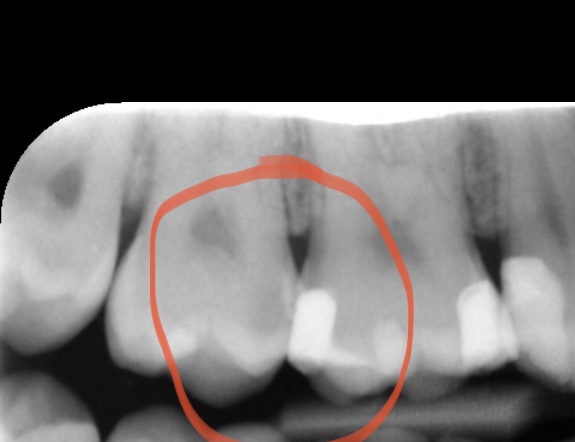

Author: Christel123 Posted: za, 03/14/2020 - 18:19 Ik kan misschien beter een abonnement op dit forum nemen, haha, maar ik wilde weten of op deze foto van mijn tand een gaatje te zien is? Alvast bedankt! Attach Lieneke In de linker kies van de In de linker kies van de omcirkeling; ja. Stuur privébericht Login of registreer om te reageren zo, 03/15/2020 - 16:09 Permalink Christel123 Als antwoord op In de linker kies van de door Lieneke In de linker kies van de Dankjewel! Dan weet ik iig dat de tandartsrekening gewoon klopte! Stuur privébericht Login of registreer om te reageren zo, 03/15/2020 - 18:32 Permalink 170 weergaves

Lieneke In de linker kies van de In de linker kies van de omcirkeling; ja. Stuur privébericht Login of registreer om te reageren zo, 03/15/2020 - 16:09 Permalink

Christel123 Als antwoord op In de linker kies van de door Lieneke In de linker kies van de Dankjewel! Dan weet ik iig dat de tandartsrekening gewoon klopte! Stuur privébericht Login of registreer om te reageren zo, 03/15/2020 - 18:32 Permalink